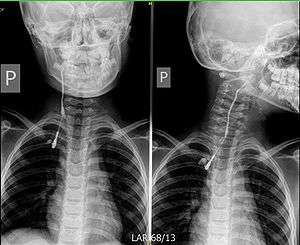

Fistulography of a right branchial cleft sinus. | |